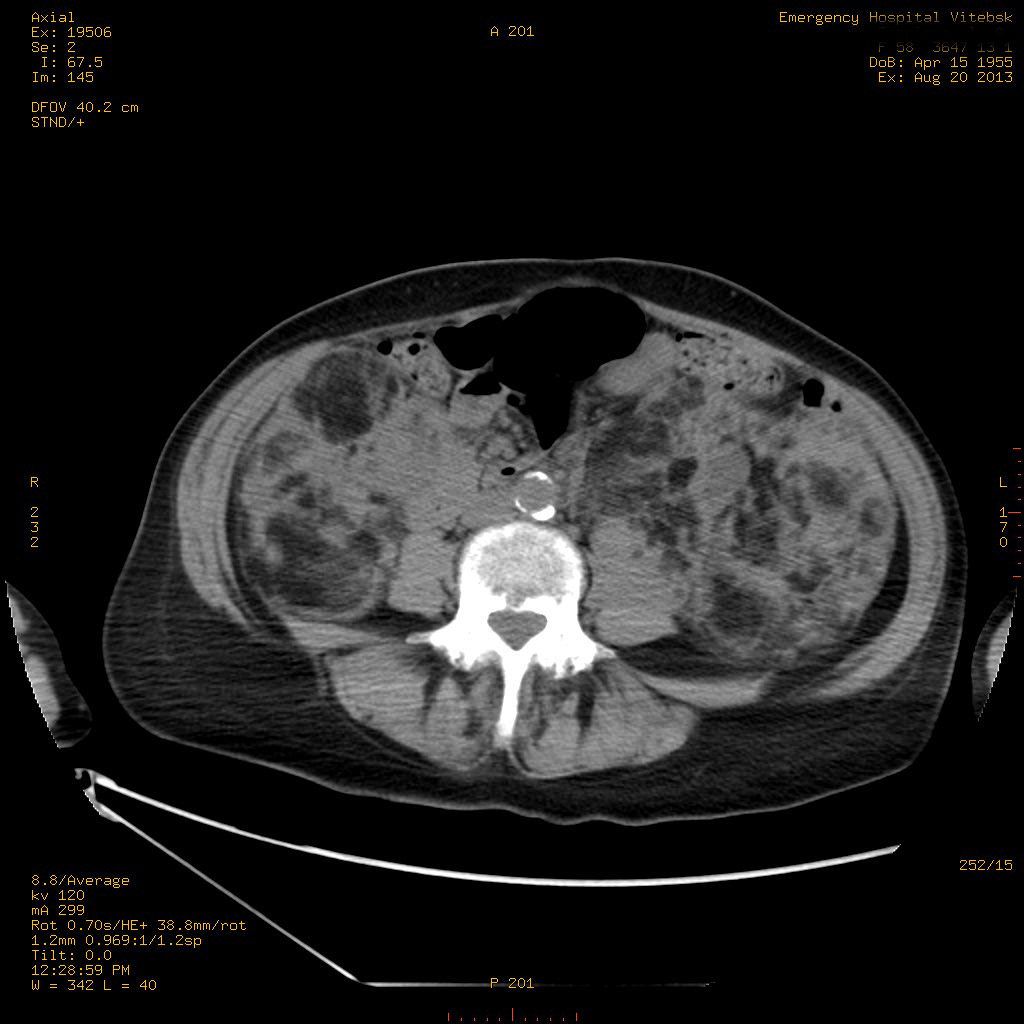

УЗИ почек - туберозный склероз

Пожилая женщина с нормальными мочевиной и креатинином.

Ангиомиолипоматоз почек , думаю компонент туберозного склероза.

Да, туберозный склероз.

Случай консультирован на кафедре радиологии Католического университета г.Лёвен (Бельгия) - зав каф. профессор Р.Оуен.